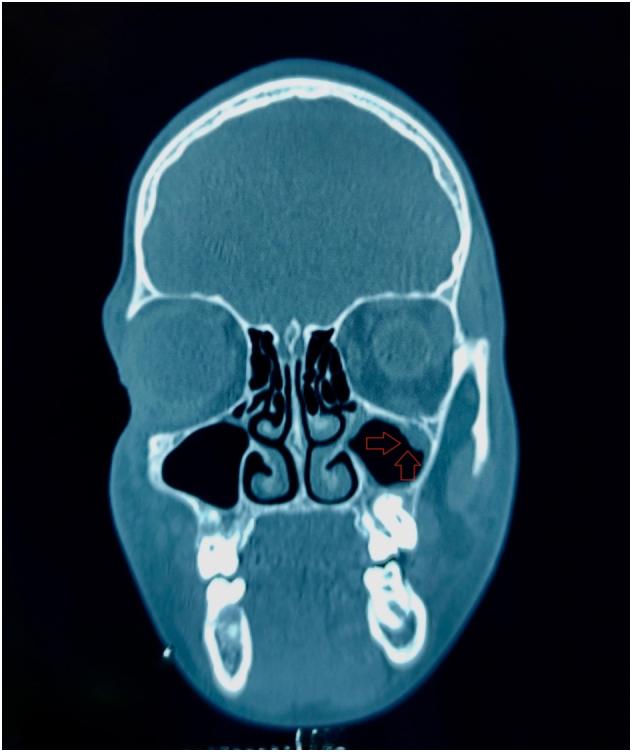

The authors report a ten years-old male child, reported to the oral and maxillofacial surgery department, Ibn Rochd university hospital, Casablanca, Morocco. The child was diagnosed for left orbital floor fracture, complaining of orbital trauma due to road accident. The injury occurred at the left orbit level. There was no general story of any disease.

In more than 40% of all the facial fractures parts of the orbital rim or/and the internal orbit are injured with a variety of fracture patterns. Accurate assessment is required in order to correct any bone defects or displacements. The surgical approaches have become more reduced offering better control of orbital pathological processes. Orbital lesions are precisely localized through imaging. Also, the approach decision depends on location, size and vascularization. No consensus exists regarding the timing of the repair, the repair technique and the optimal implant. In this case presentation, the defect on the orbital floor was extended by mobilization of the fragments. A combination of incisions was necessary due to the change in the dimensions of the defects intraoperatively and entrapment of orbital tissue by the placement of an implant.